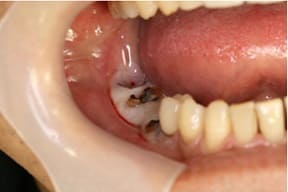

CASE03 臼歯部インプラント ~ブリッジがグラつき始めている~

ブリッジの部分の下顎の骨が吸収をおこし、ブリッジで支えている歯がぐらつき始めている状態。予後を考えた結果、ブリッジで支えることが困難という診断のもと、インプラント治療を施したケースです。